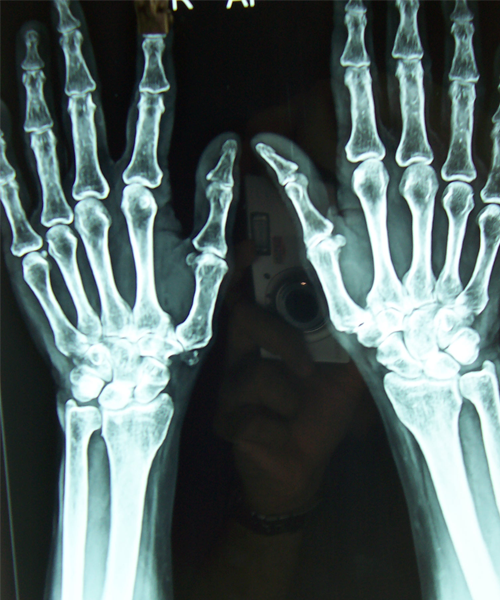

Case:5 RollTendon Arthroplasty

Arthroscopy Surgeon in Ahmedabad|Limb Reconstruction Doctor

Pre-Op

Arthroscopy Surgeon in Ahmedabad|Spine Treatment In Jaipur

Post-Op